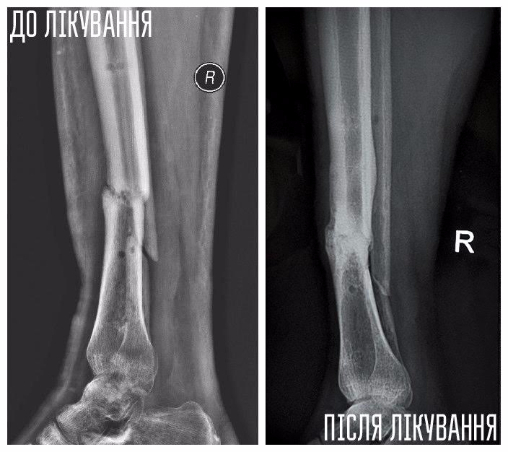

Обстеження у клініці показало, що його реабілітація проходить успішно.

Юрій — боєць 51 ОМБр, травму отримав у липні 2014 року під Слов'янськом. Авто, яким кермував Юрій, підірвалося на ворожому фугасі, осколками тяжко травмувало руку і ногу хлопця. Юрія лікували у трьох шпиталях, та навіть за рік зусиль лікарів кістки гомілки не зрослися.У місці перелому почав формуватися несправжній суглоб, ногу тяжко викрутило — хлопець ледве пересувався навіть на милицях.

Влітку 2015 року, завдяки порадам та допомозі волонтерів, Юрій долучився до «Біотеху».